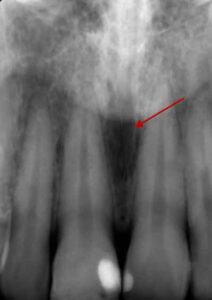

歯科X線写真における正常な解剖学_図8a